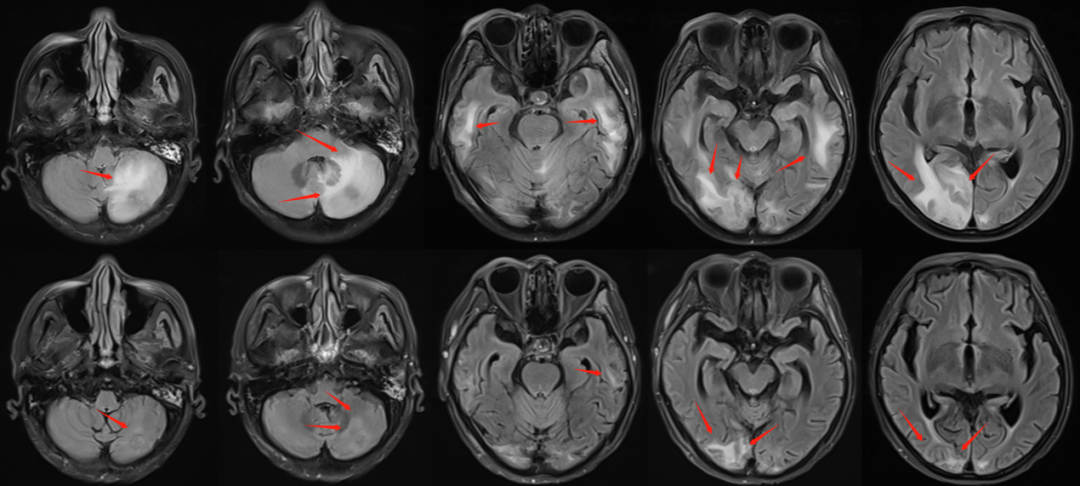

經(jīng)過3周(15次)次放療,患者病情得到良好控制。復(fù)查磁共振檢查可見腦內(nèi)病灶明顯縮小,大部分消失;瘤周水腫基本消散。證明腫瘤病灶活性喪失,得到徹底控制;也說明治療劑量方案得當(dāng),患者沒有發(fā)生放射性腦損傷。單次治療不足3分鐘,過程順利,患者無明顯不良反應(yīng)發(fā)生。療后復(fù)查病灶完全控制,患者安返內(nèi)蒙古老家。

圖注:治療3周后復(fù)查磁共振顯示,T1增強(qiáng)掃描可見顱內(nèi)強(qiáng)化轉(zhuǎn)移病灶較前明顯縮退,部分消失。并且,放療后病灶仍將進(jìn)一步消退。

圖注:治療結(jié)束時(shí)復(fù)查磁共振顯示,T2FLARE像可見轉(zhuǎn)移瘤周水腫基本消退。說明腫瘤病灶活性喪失,得到徹底控制;也說明沒有放射性腦損傷發(fā)生。